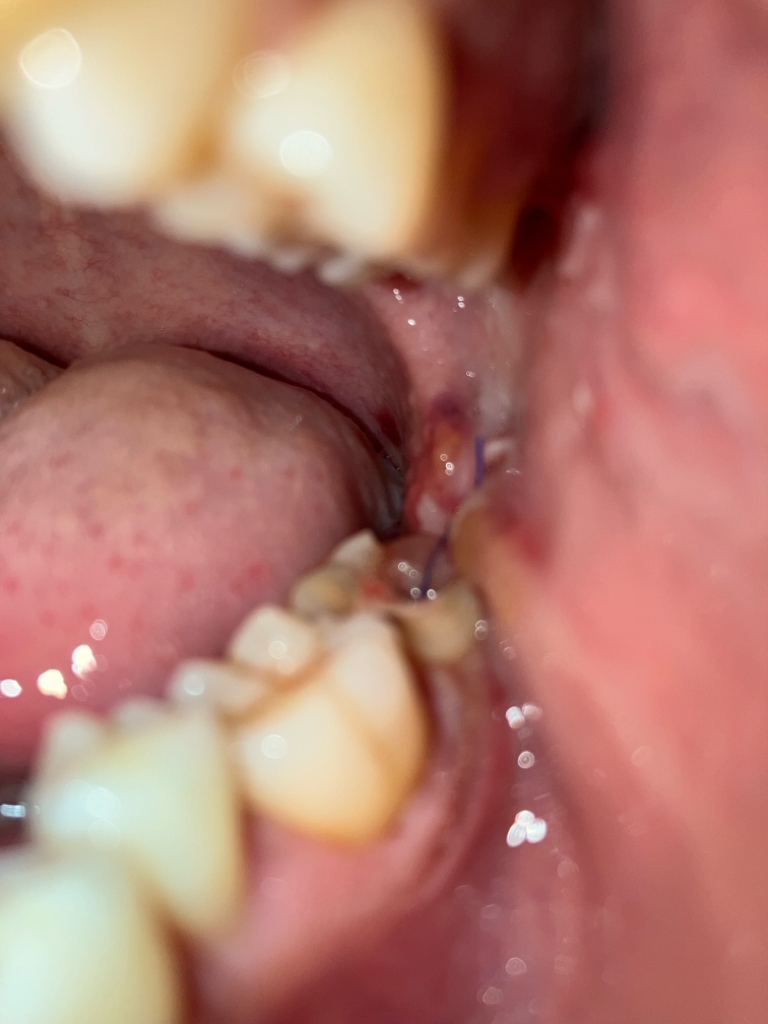

매복사랑니 발치를 하시고 나서 아직은 잇몸이 많이 부어 잇는거 같습니다. 흡연은 실밥 푸실때까지 피해주시는게 좋을것같습니다.

매복사랑니를 발치한 경우 7일간은 해당부위에 염증이 덧나지 않도록 흡연 및 음주는 반드시 피하길 권합니다.

사랑니를 발치한 부위가 아물기 위해서는 2주 정도가 걸리게 됩니다. 그 이전에 흡연을 하게 되면 해당 부위의 혈병이 제거가 되기 때문에 치유가 늦어질 수 있어서 권유하지 않습니다. 최소한 일주일 동안은 금연을 하는 것을 권유드립니다